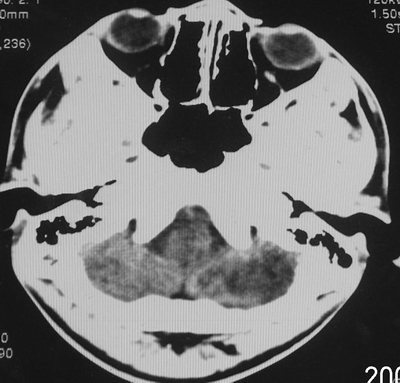

患者、男、18y,头痛5天入院。

左小脑、右丘脑区低密度影,无明显强化及占位表现,男18y,先考虑脑部炎性病变,如脑炎、血行播散性感染等,建议结合临床如脑脊液检验。

单独看左侧小脑半球的不规则形囊性低密度灶,从发病部位、年龄以及无强化、无占位效应的特点可以考虑毛细胞瘤型星形细胞瘤。同样,如果单独看右侧丘脑的近圆形低密度,也可以考虑囊变形星形细胞瘤。只是胶质细胞瘤一般为单发直接浸润、蔓延生长,而不是在脑内同时出现多个病灶,且瘤周没有一点儿水肿,暂时不予以考虑。

同时,现在已经进入冬天,一氧化碳中毒也需要考虑进去。不知道增强是什么时间做的,与平扫间隔几天?如果中间时间比较久而且进行吸氧等治疗,则平扫所示右侧颞叶密度比较低、右侧小脑半球以及脑桥也似有片囊状低密度,但在增强却没有发现就可以比较合理的解释了。

左侧小脑半球及右丘脑低密度影,考虑炎症可能性大

左侧小脑半球及右丘脑低密度影,考虑  1、脑梗塞灶. 2、占位性病变,建议作mri检查

考虑耳源性脑脓肿.